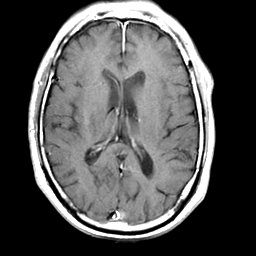

Meningioma, MR Study #2 -- Slice #11

[Home][Help][Clinical] Slice 11